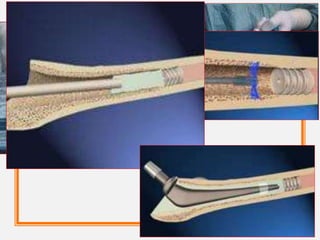

• The centralizers bond to the new cement and are

incorporated into the cement mantle.

MODERN CEMENTING

TECHNIQUE

Vacuum mixing of bone cement

Pulsatile lavage cleaning

Medullary canal restrictor

Cement Gun & Proximal femoral pressurisation

Acetabular cement pressurisation

Use of proximal and distal stem centralizers.